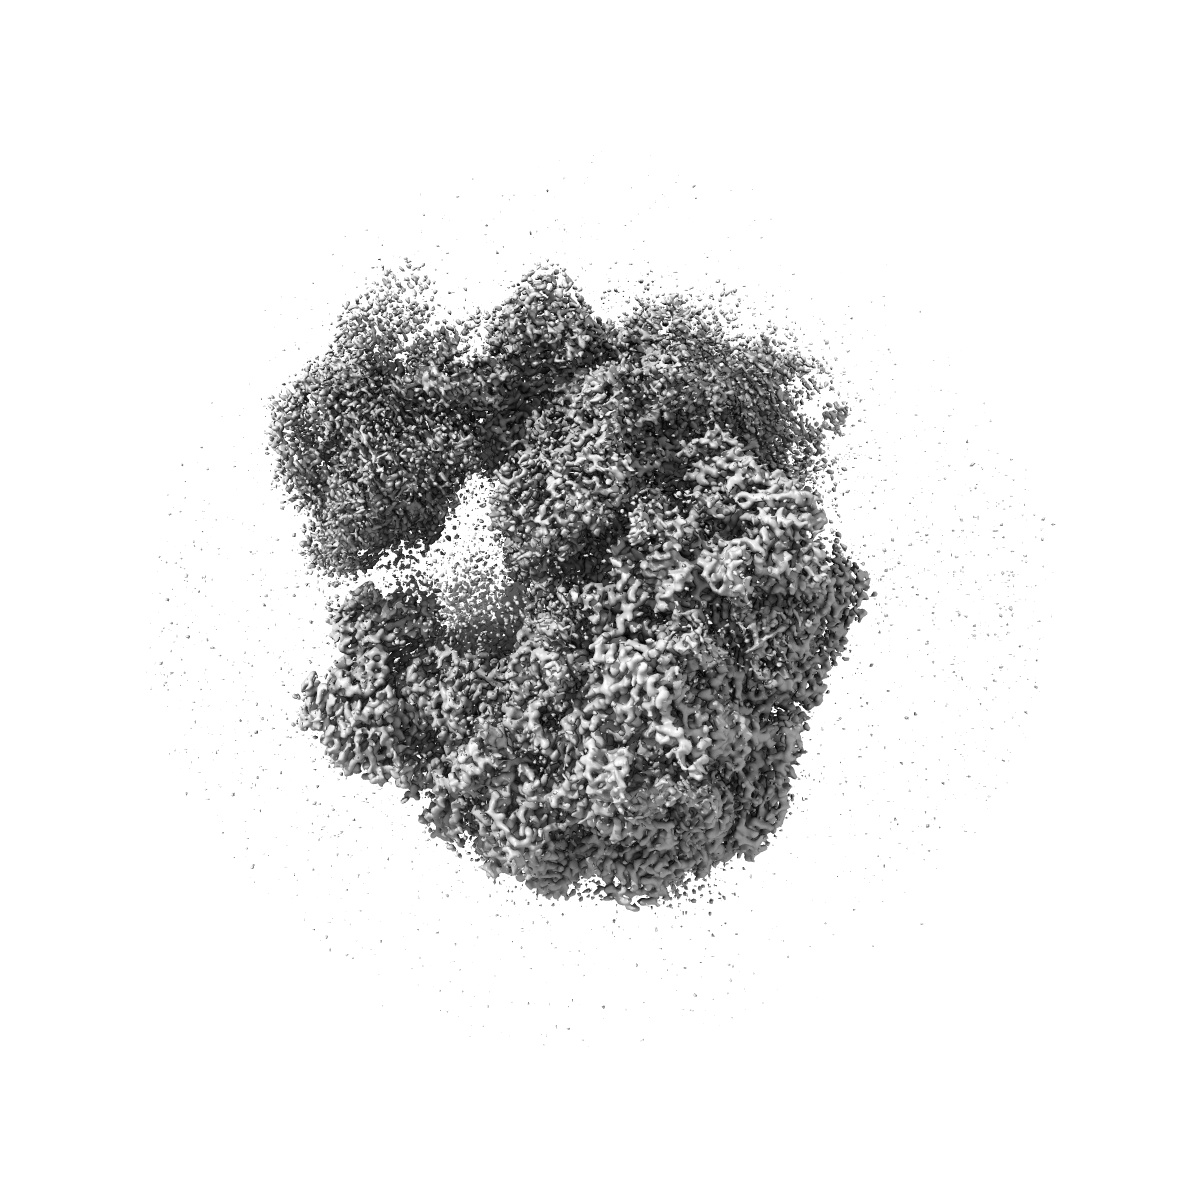

Cryo-EM map of Candida albicans 80S ribosome in complex with mefloquine (non-rotated state)

Single-particle3.1 Å

Sample: Candida albicans 80S ribosome in complex with mefloquine (non-rotated state)

Mechanism of read-through enhancement by aminoglycosides and mefloquine.

(2025) PNAS , 122 , e2420261122 - e2420261122